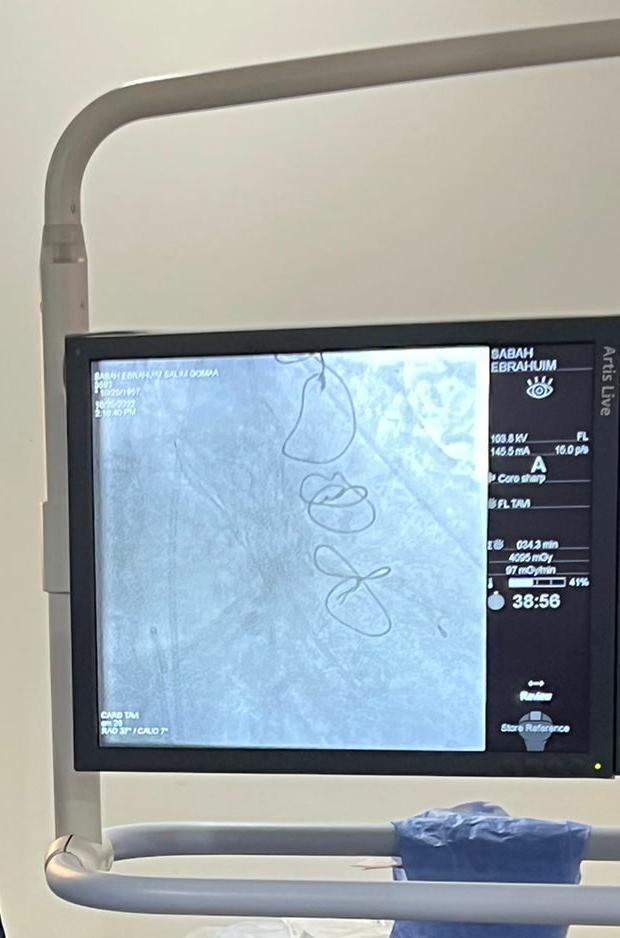

أعلنت الهيئة العامة للرعاية الصحية، عن نجاح عملية جديدة لاستبدال وزراعة الصمام الأورطي لمريضة عن طريق القسطرة باستخدام تقنية التافي TAVI، وذلك بمجمع الإسماعيلية الطبي التابع للهيئة بمحافظة الإسماعيلية.

وأشار الدكتور أحمد السبكي، رئيس الهيئة العامة للرعاية الصحية، مساعد وزير الصحة والسكان، المشرف العام على مشروع التأمين الصحي الشامل، إلى أن تقنية "التافي"هي من أحدث التقنيات العلاجية العالمية المستخدمة في علاج أمراض القلب، لاستبدال أو زراعة الصمام الأورطي، والتي تعني استبدال الصمام دون شق منطقة الصدر، عن طريق القسطرة دون تدخل جراحي.

ولفتت هيئة الرعاية الصحية، إلى إجراء عملية استبدال وزراعة الصمام الأورطي عن طريق التافي TAVI لمريضة تبلغ من العمر 67 عامًا، تعاني من ضيق حرج فى الصمام الأورطي، وأمراض مزمنة الضغط والسكري إضافة إلى السمنة المفرطة ومرض السدة الرئوية، وسبق وأن أجريت لها عملية قلب مفتوح وعمل وصلات للشرايين التاجية في عام 2014، ولذا كان الخيار الأمثل هو إجراء عملية استبدال الصمام الأورطي للمريضة عن طريق تقنية التافي، للحفاظ على حياتها.